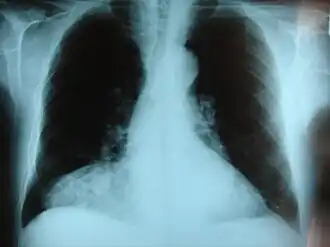

Radiografía frontal del pecho mostrando una hernia de Morgagni.